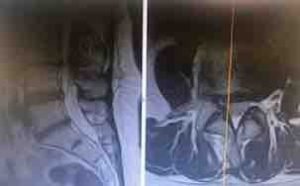

Esta vez y gracias a la Colaboración del Dr. Fernando Héctor Estol, Anestesista del Hospital Universitario HM Puerta del Sur, se ha podido realizar esta cirugía de raquis con anestesia raquídea y sedación. Se realizó una foraminoplastia endoscópica transforaminal TESSYS de Joimax. Paciente con discopatía severa L3-L4 con estenosis del receso derecho que tras tratamiento conservador y técnicas del dolor no mejoró de los síntomas. Se decidió realizar esta cirugía tras agotar el tratamiento conservador y no obtener mejoría. El procedimiento duró apenas 60 minutos, y la paciente inicio deambulación 4 horas después de la intervención. En menos de 24 horas tras la cirugía la paciente se fue de alta hospitalaria con mínimas molestias.

Estenosis del receso L3-L4 lado derecho